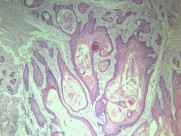

鳞癌是鳞状细胞癌(squamous cell carcinoma)的简称,常发生在身体原有鳞状上皮覆盖的的部位,如皮肤、唇、口腔、食管、喉、子宫颈、阴道、阴茎等处。有些部位如支气管、胆囊、肾盂等处,鳞状细胞癌:高分化,可见角化珠正常时不是由鳞状上皮覆盖,但可通过病理演变鳞状上皮化生…